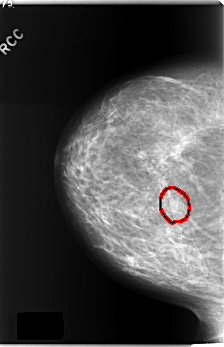

C_0240_1.RIGHT_MLO

RIGHT_CC LINES 5896 PIXELS_PER_LINE 3800 BITS_PER_PIXEL 12 RESOLUTION 50 OVERLAY

FILE: C_0240_1.RIGHT_CC.OVERLAY

TOTAL_ABNORMALITIES 1

ABNORMALITY 1

LESION_TYPE MASS SHAPE OVAL MARGINS ILL_DEFINED

ASSESSMENT 4

SUBTLETY 3

PATHOLOGY BENIGN

TOTAL_OUTLINES 1

BOUNDARY